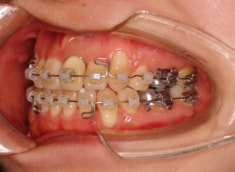

治療開始時

治療開始から約1年後